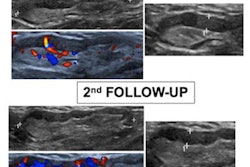

A team led by Dr. Costantino Caroselli from the National Institute of Rest and Care for the Elderly in Ancona found that ultrasound characteristics seen in COVID-positive patients included B-lines, irregular pleural lines, and small consolidation.

Lung POCUS was performed by trained emergency physicians on patients presenting for possible COVID-19 evaluation before they underwent conventional radiologic examination or while they were waiting for the report.